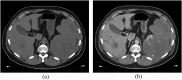

Angiosarcoma is a rare, aggressive subtype of soft-tissue sarcoma with a propensity for local recurrence and metastasis associated with a generally poor prognosis, unless diagnosed early. Given the vascular endothelial cell origin of angiosarcoma, tumours may develop in essentially any organ; however, there is a predilection for the skin where half of all tumours arise, increasing in prevalence with age. The most common risk factors are chronic lymphoedema and history of radiation. We review the most important radiological findings along the spectrum of angiosarcoma from head to toe throughout the body, including uncommon and rare locations. Key imaging features of angiosarcoma across multiple organ systems will be described, as well as the impact on management and prognosis.

- Peterson MS, Baron RL, Rankin SC. Hepatic angiosarcoma: findings on multiphasic contrast-enhanced helical CT do not mimic hepatic hemangioma. AJR Am J Roentgenol 2000; 175: 165–70. doi: https://doi.org/10.2214/ajr.175.1.1750165 - DOI - PubMed